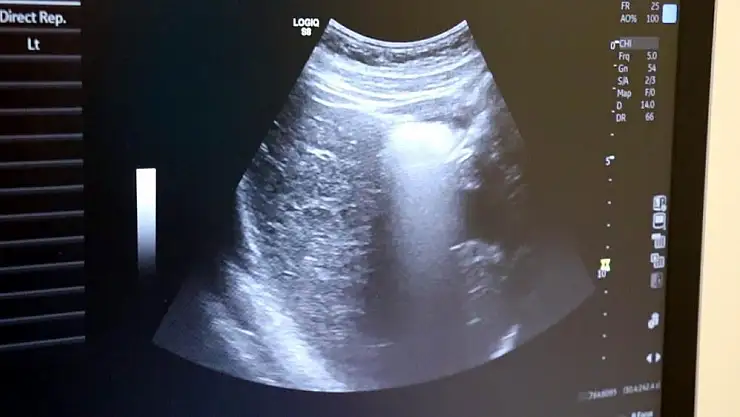

Ultrason uzun zamandan beri özellikle gebe annelerde sıklıkla başvurulan bir görüntüleme yöntemi. Yüksek ses frekanslarının işlenip ekrana yansıtılması ile elde edilen görüntülerle bebeğin sağlık durumunun yanı sıra birçok bilgiye de ultrason sayesinde erişmek mümkün olabiliyor. Dr. İlker Eroğlu, 2 boyutlu ultrasonun ve 4 boyutlu ultrasonun hiçbir zararı olmadığını belirterek açıklamalarda bulundu.

Ayrıntılı ve 4 boyutlu ultrason ile bebeklerin doğmadan önceki sağlık durumlarının belirlenebileceğine değinen Uzm. Dr. İlker Eroğlu, “Ultrason; yüksek frekanslı ses dalgalarının bilgisayar işlemcisinde işlenip, kablo arayıcılığıyla monitöre aktarılmasıdır. Son yıllarda gebelikte ayrıntılı ultrason gerekliliği giderek artmaktadır. Yaklaşık 50 yıl önce ultrason yaygın değilken doğumlarda bebek nasıl doğacak, sağlıklı mı sağlıksız mı doğacak ya da cinsiyet bile bilinemiyordu. 4 boyutlu ultrasonda ya da ayrıntılı ultrasondan sonra bebeğin sakatlıkları doğumdan önce anlaşılıp, tedavisi mümkün olanlar da doğumdan önce tedavi edilebilir oldu. Böylelikle bebeklerin daha sağlıklı olarak dünyaya gelmesi sağlanmış oldu. O nedenle ayrıntılı ultrason gereklidir” dedi.

Renkli ultrasonlarda bebeklerin anne karnındayken sakatlığı olup olmadığının belirlendiğini ifade eden İlker Eroğlu, “4 boyutlu ultrason halk arasında ‘renkli ultrason’ diye bilinir. Anneler bu ultrasonda bebeğin görüntüsünü anladığı için onu daha çok sever. Hekimler genelde ultrasona siyah-beyaz bakar. 4 boyutlu ultrason iç organlar hakkında detaylı bilgi vermez. Biz detaylı ultrasonda (2. düzey ultrason) bebeğin iç organlarına yönelik incelemeyi siyah beyaz olarak yaparız. O nedenle bizim için siyah-beyaz ve 2 boyutlu olarak yapılan inceleme daha önemlidir. 4 boyutlu ultrasonda da faydalandığımız yerler vardır. 4 boyutlu ultrasonda örneğin; bebeğin kolu-bacağı yoksa, dudak yarığı varsa, gösterebiliriz. Çeşitli anatomik deformasyonları da anneye gösterebiliriz. Hala dünyada ayrıntılı ultrason 2 boyutlu ve siyah-beyaz olarak yapılır” diye konuştu.